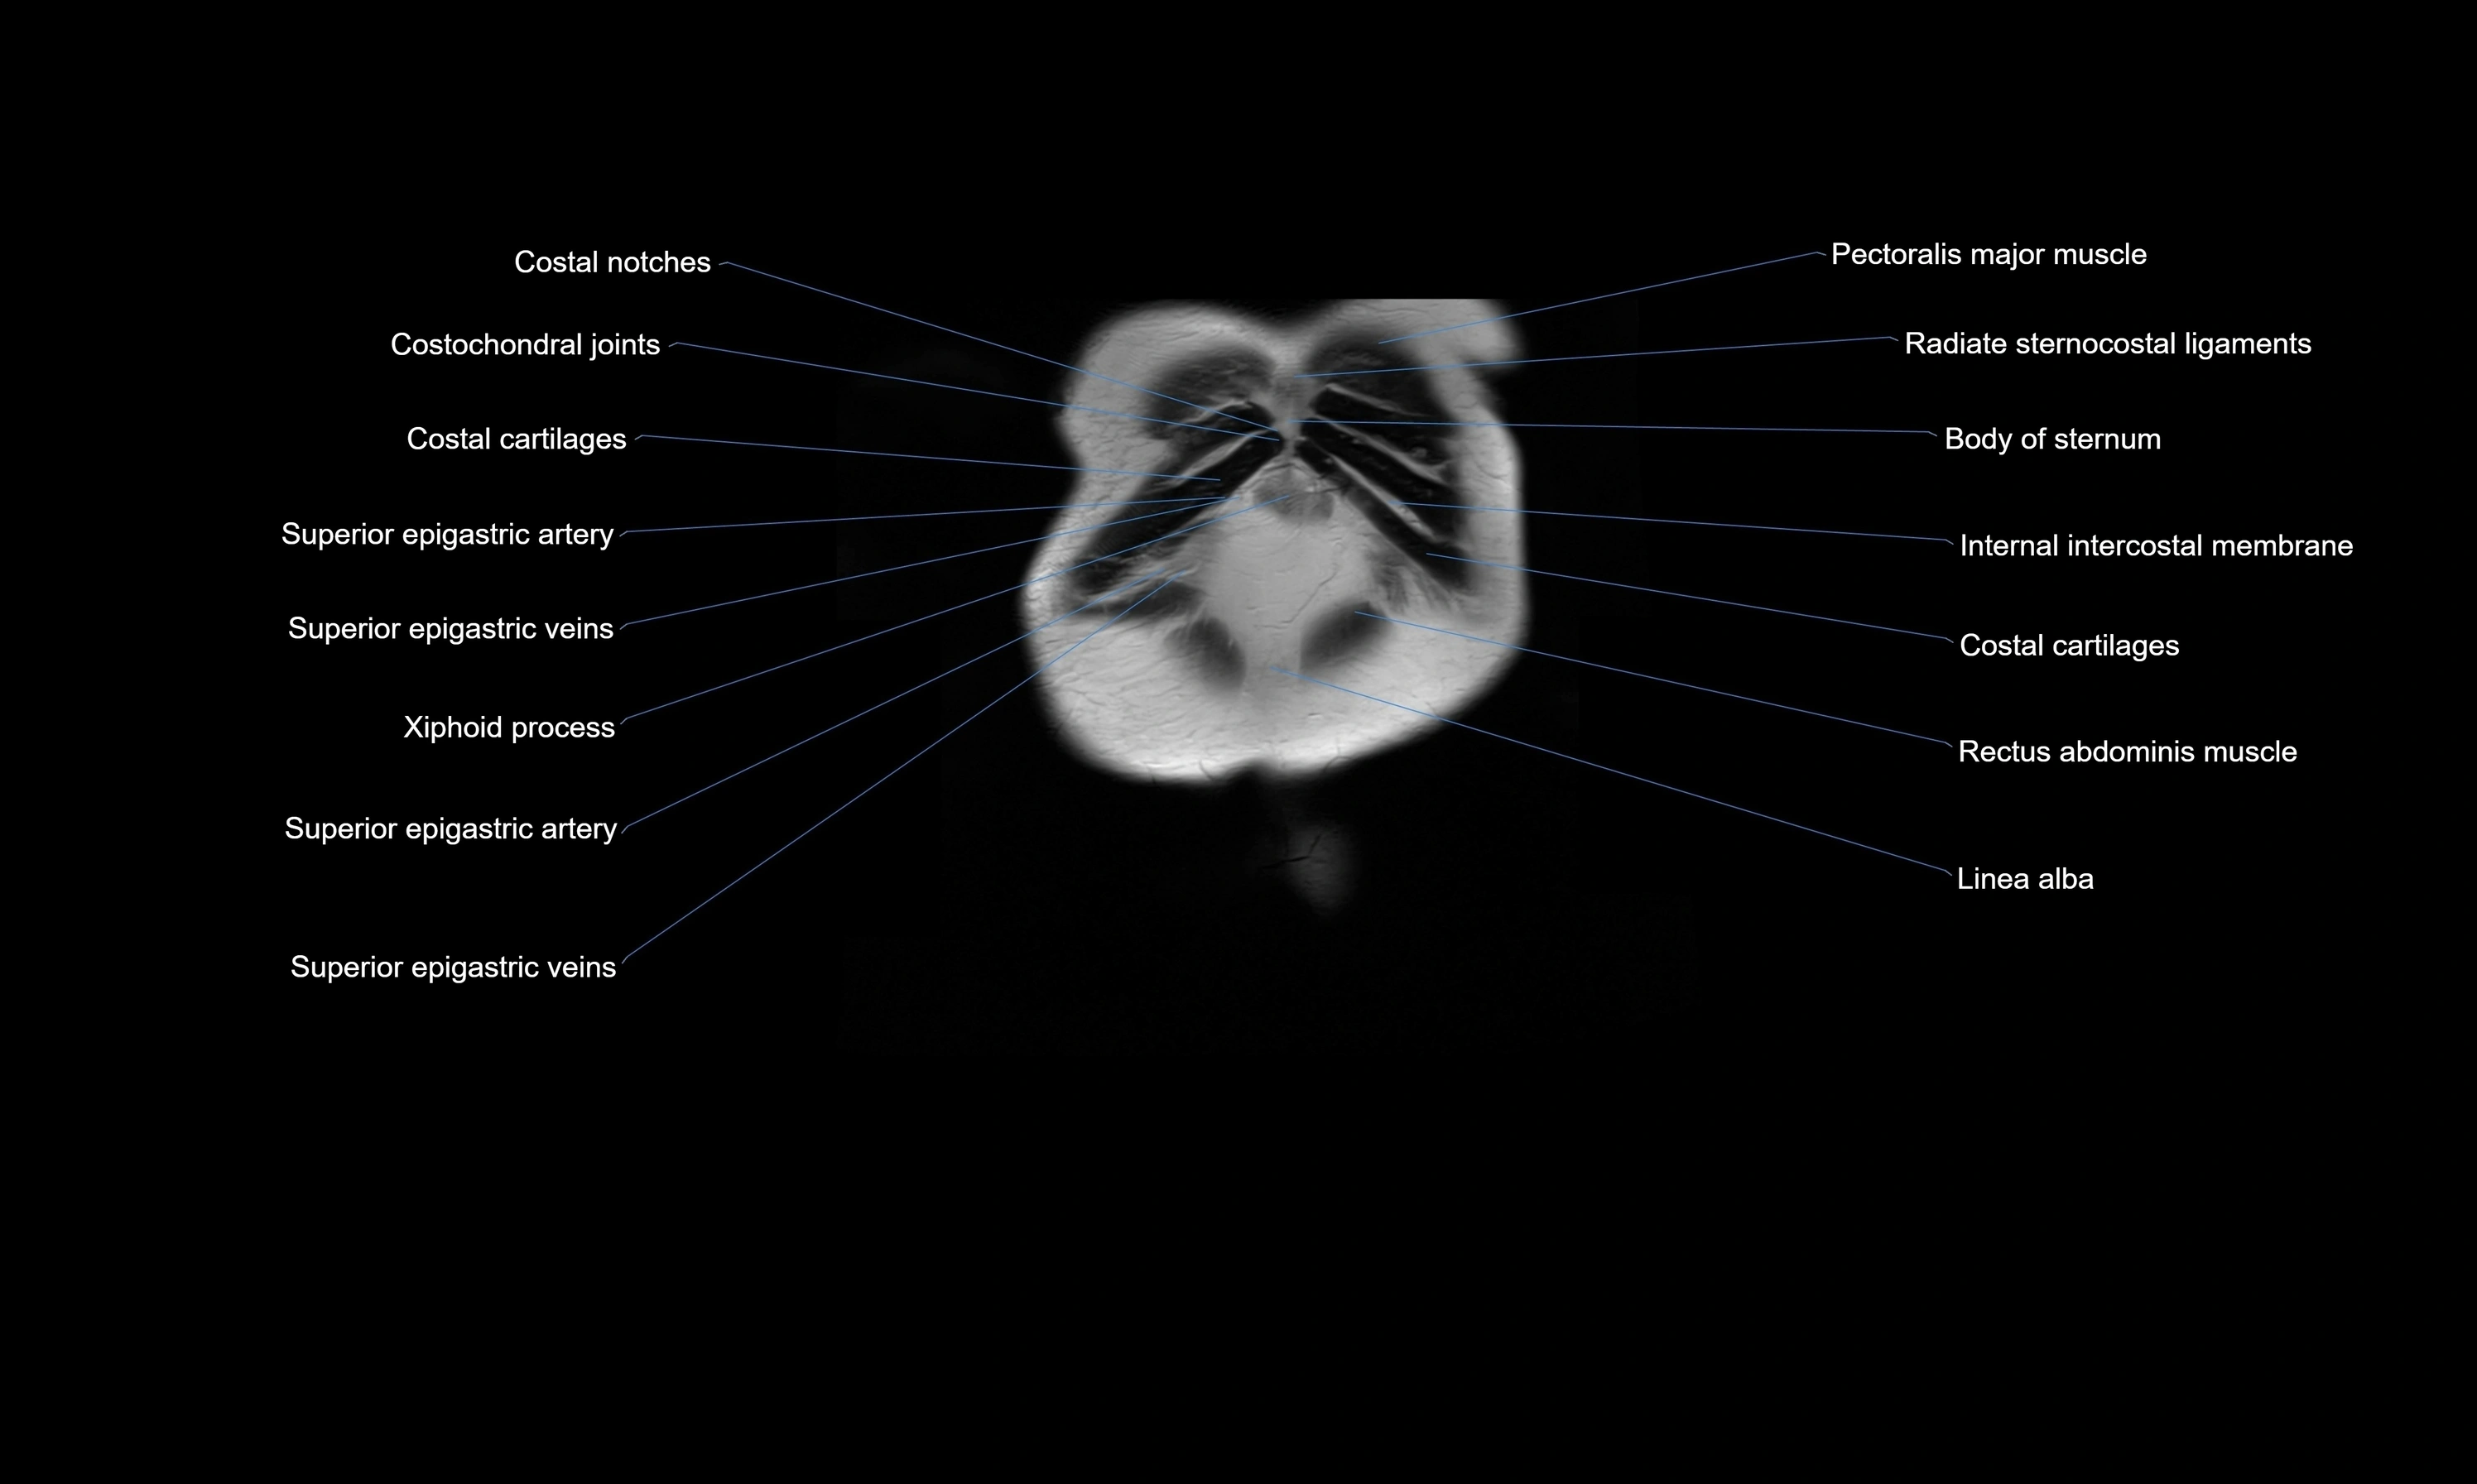

MRI images